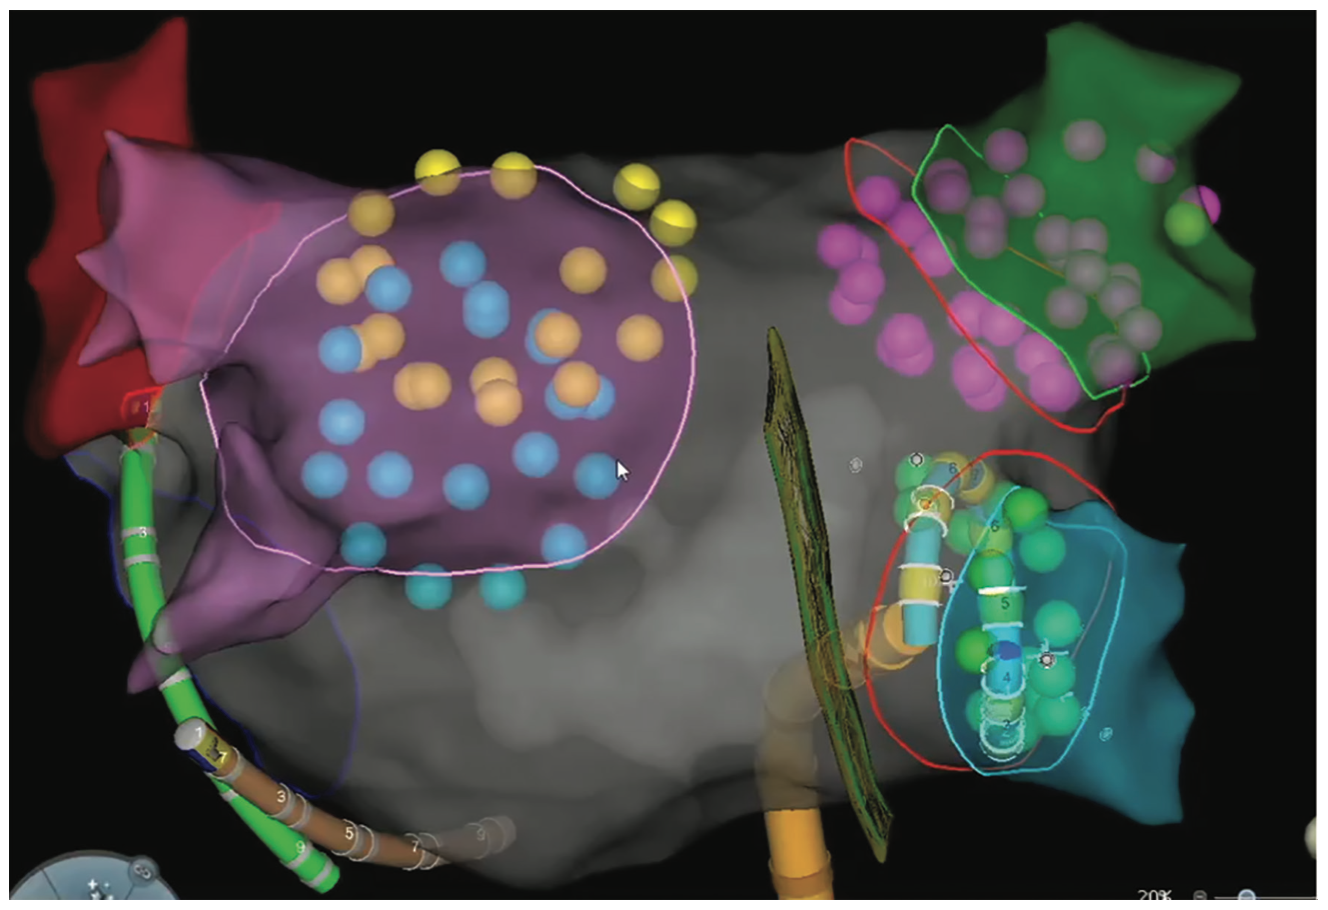

Reddy et al reported the first clinical experience in 22 patients with paroxysmal AF using pulsed electric field ablation for PVI (15 endocardial and 7 epicardial).25 Catheter-based PV isolation using the Farawave catheter was 100% successful using a total electroporation delivery time of less than 60 seconds per patient (Figure 1). The epicardial box lesion was done using a linear catheter around the PVs and successful in 86% of patients using 2 lesions per patient. The IMPULSE (n = 40) and PEFCAT (n = 41) trials also examined patients with paroxysmal AF using both monophasic (IMPULSE) and biphasic (PEFCAT) waveforms with the Farawave catheter.26 PVI was achieved in 100% of patients, with no reconnections noted during the 20-minute waiting period or with provocative adenosine testing. Monophasic waveforms required general anesthesia and paralytic agents because of profound skeletal muscle contraction. The biphasic waveform cases were better tolerated due to less contraction and performed under conscious sedation. In follow-up, no patients had phrenic nerve palsy, esophageal injury, or PV stenosis.27 A 1-year follow-up study showed durable PVI in 84.8% of PVs remapped at 90 days in 110/121 patients in the IMPUSE, PEFCAT, and PEFCAT II studies.28 Freedom from atrial arrhythmias at 1 year in the entire cohort was 78.5 ± 3.8%. The PULSED AF Pilot Trial (n = 38) for paroxysmal AF using the PulseSelect PFA System (Medtronic) also showed 100% acute PV isolation with no adverse events such as phrenic nerve injury, esophageal injury, or stroke.29 The single-arm, multicenter PersAFOne study in persistent AF patients from Homolka Hospital in Prague, Czech Republic, and Clinical Hospital Center Split in Split, Croatia, used the pentaspline Farawave catheter for PVI and posterior wall isolation (PWI) and a focal PFA catheter (Faraflex, Boston Scientific) for cavotricuspid isthmus (CTI) ablation.30 Acute isolation of the PVs and PW was achieved in all 25 patients and CTI block was achieved in 13/13 patients. Postprocedural esophagogastroduodenoscopy and computed tomography scans showed no evidence of esophageal injury or PV stenosis. Invasive remapping in 22/25 patients showed 96% of PVs isolated at 3 months and 21/21 PWs were isolated. Another trial that used the lattice tip catheter in a first-in-human experience showed that the Sphere-9 catheter could be used to toggle between RF and PFA or use PFA alone in both paroxysmal and persistent AF patients with good efficacy and safety.31 Loh et al similarly showed that PFA using a proprietary 14-polar single-shot circular catheter could achieve acute bidirectional isolation in 10 patients in another first-in-man study.32

In the United States and internationally, there are over 20 trials listed as active on www.clinicaltrials.gov for PFA in patients with AF. Many of the trials are exclusive to international sites in Europe or Asia. Three clinical trials with sites in the United States are active and recently finished recruiting. The ADVENT trial compared the Farapulse PFA System to current standard of care ablation systems (RF or cryoablation) in paroxysmal AF. The PULSED AF study was a single-arm study using the PulseSelect PFA System in either paroxysmal or persistent AF patients (Figure 2). The admIRE study evaluated a circular multielectrode PFA catheter (VariPulse, Biosense Webster, Inc, a Johnson & Johnson company) in a single-arm study of paroxysmal AF patients (Figure 3). Ongoing and actively recruiting studies include the Sphere-9 lattice PF/RF system compared to RF ablation in a 1:1 randomization in persistent AF patients in the SPHERE Per-AF trial.